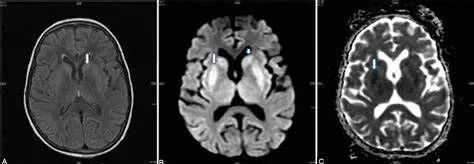

(2)CPM,病灶多位于桥脑基底部而桥脑腹侧不受累,病灶形状多种多样,可为条片状(位于中脑基底部中线,如本例)、斑片状、圆形或卵圆状、「三叉戟」或「猪鼻」样,T1WI 呈低信号,T2WI 及 FLAIR 呈高信号,病灶边界清晰,部分患者出现 DWI 高信号,有利于疾病的早期发现,出现强化提示血脑屏障破坏。

“三叉戟”样病灶,桥脑腹侧及被盖未受累

(4)CPM+EPM:(2) (3),MRI 与临床表现不密切相关,一般都会滞后几个星期。